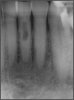

Fig 9. Significant bleeding and other problems resulted from this case.

Figure 9

Figure 9 shows a situation on tooth No. 12 that may have been presumed to be easily resolvable. However, the dentist experienced problems, including significant bleeding. It was due either to irreversible pulpitis or a perforation. Judging by the PA, something detrimental was occurring with the distal. A lesson that can be learned from this case is that a solution does not have to look pleasant for it to work. Functionally, the repair shown in Figure 10 was successful because the clinician was able to fix the whole wall with mineral trioxide aggregate (MTA) and was able to find the canal. The clinician also put in the post for the general dentist and closed it. Later, the general dentist took the post out and replaced it with a post that was larger and shorter than would be recommended. Interestingly, the result lasted 8.5 years, as shown in Figure 11.